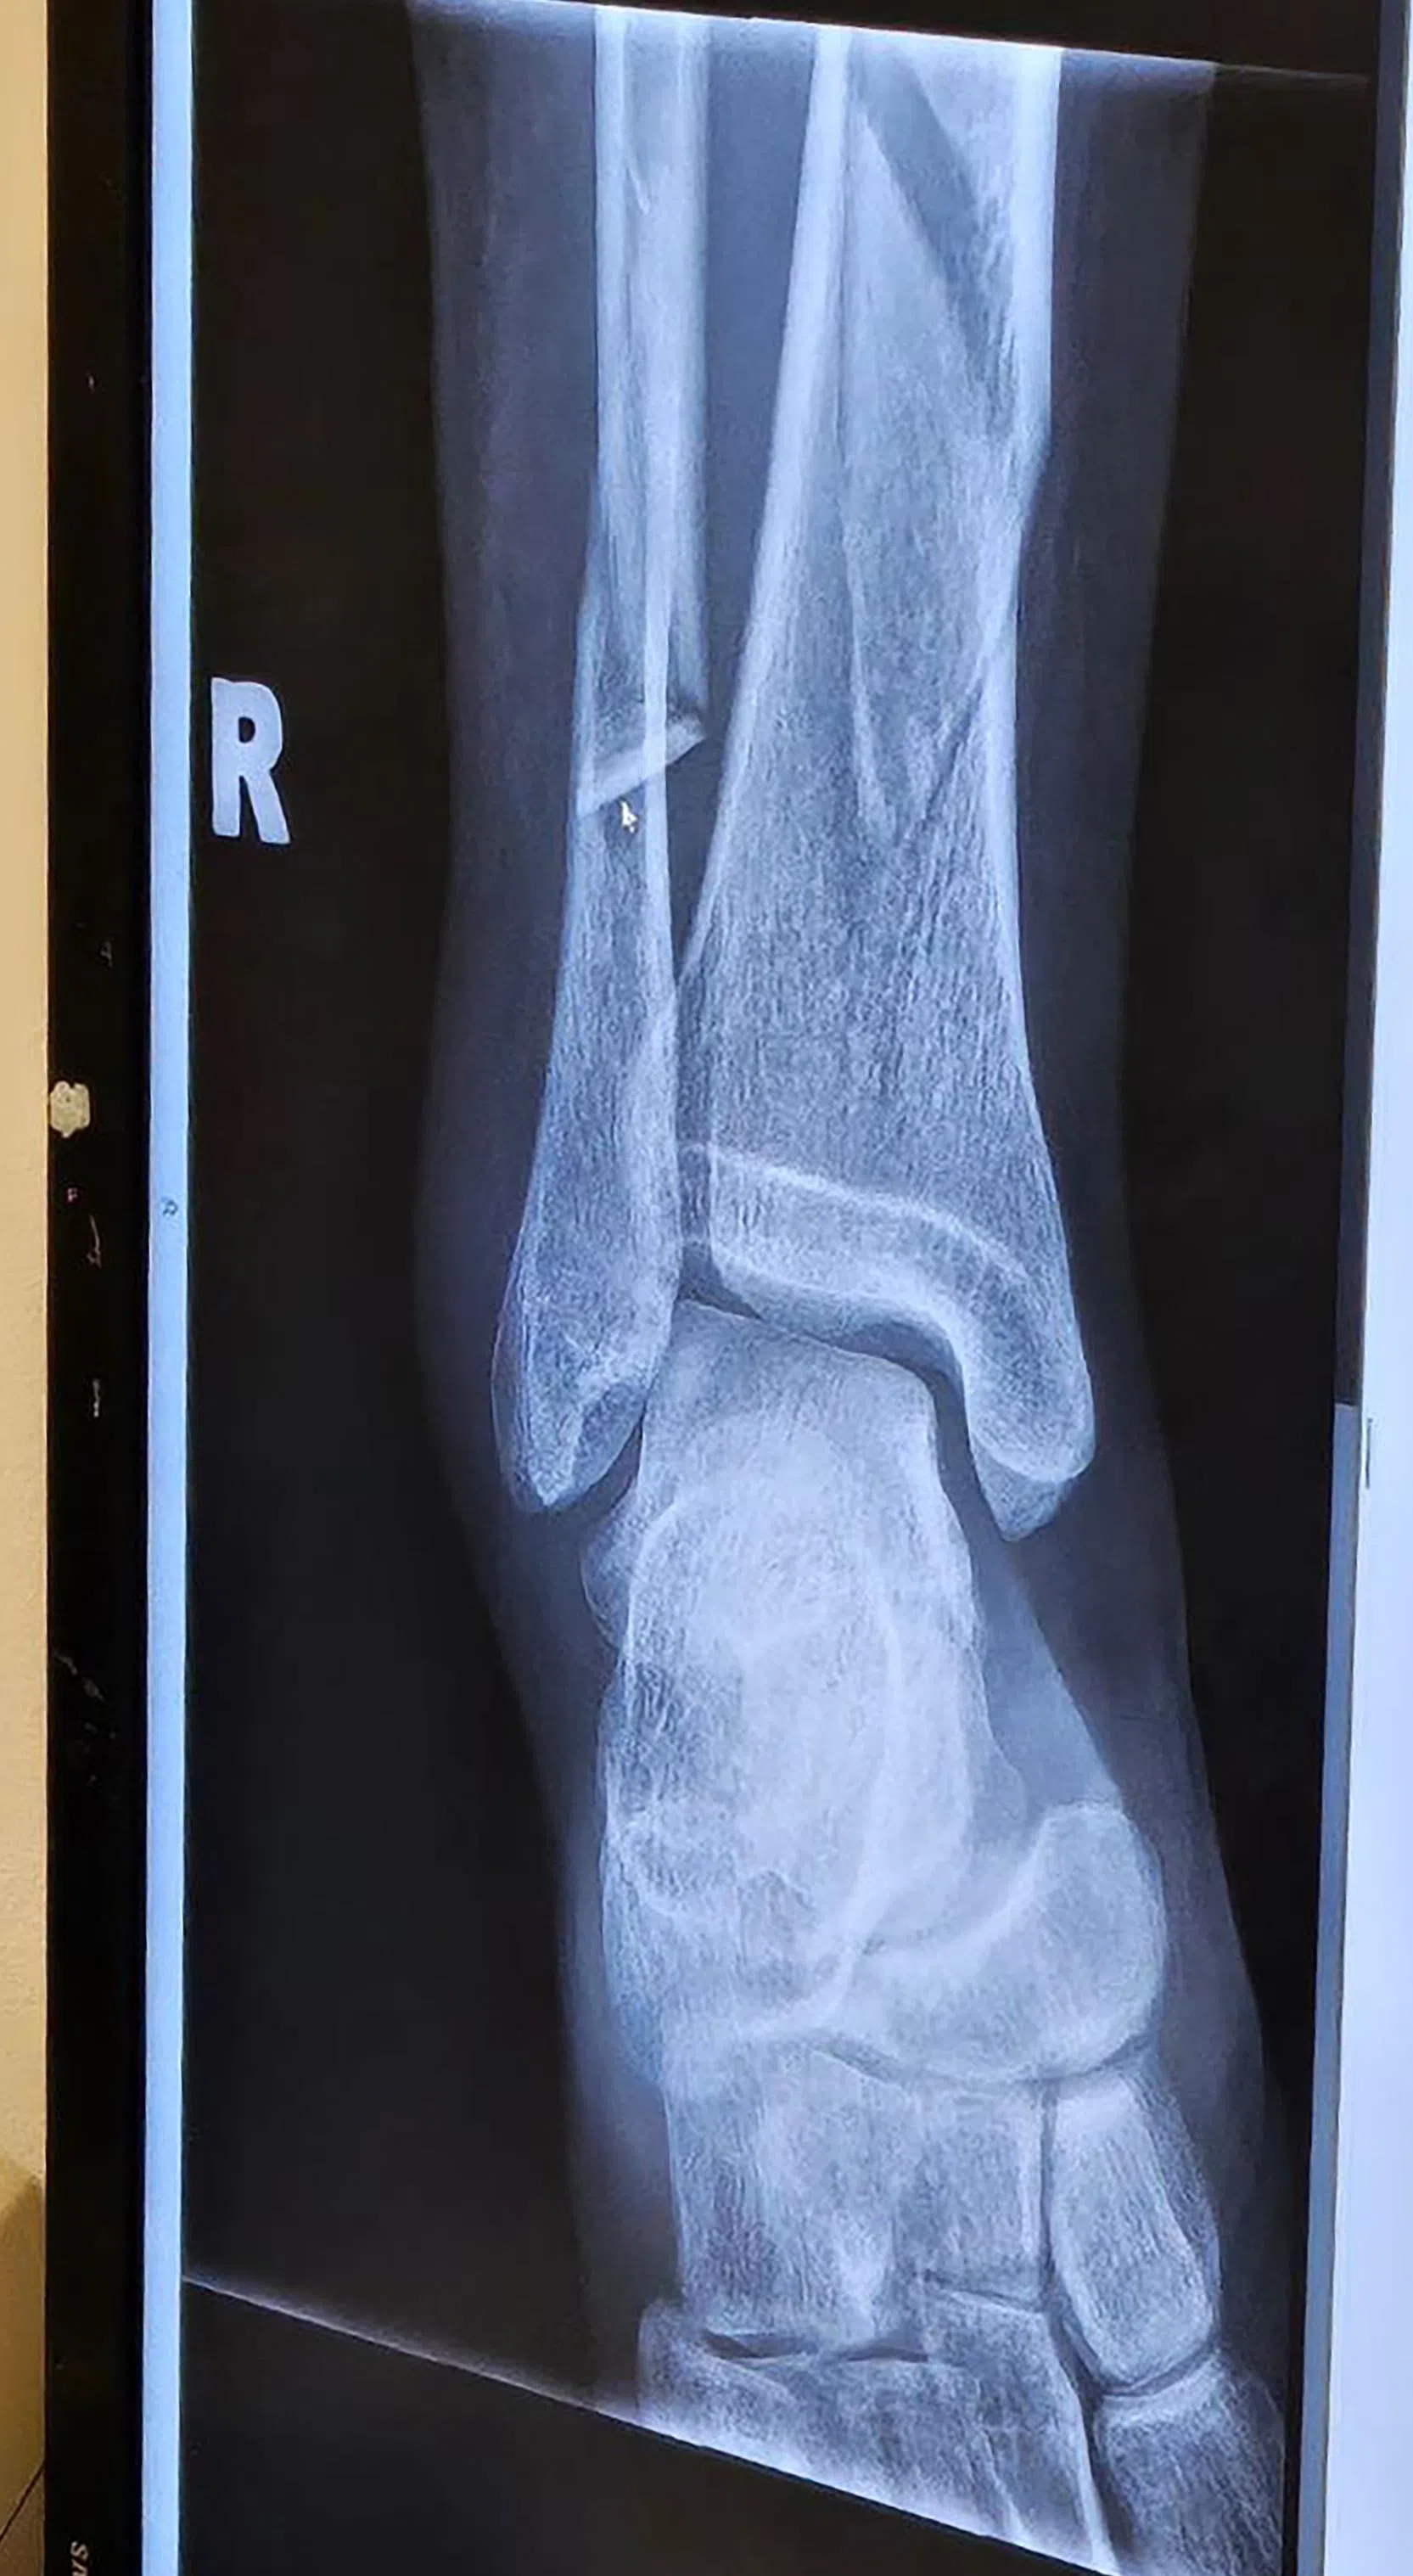

根据X光照片,女游客折断了右腿的一大一小两根腿骨。